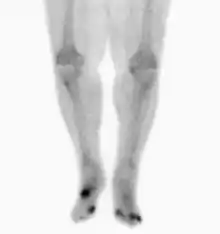

Nuclear medicine scans can be a helpful adjunct to MRI in patients who have metallic hardware that limits or prevents effective magnetic resonance. Generally a triple phase technetium 99 based scan will show increased uptake on all three phases. Gallium scans are 100% sensitive for osteomyelitis but not specific, and may be helpful in patients with metallic prostheses. Combined WBC imaging with marrow studies have 90% accuracy in diagnosing osteomyelitis.[22]